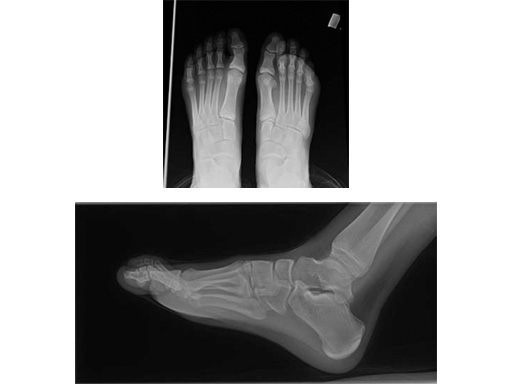

Case 2: 16-year-old male

Proximal first metatarsal growth-plate injury resulting in haluxvalgus. Arthrosis of first tarsometatarsal and second metatarsal hammer toe. Pain during activities and in general shoe wear.

Case provided by Carl Hasselman, Pennsylvania, USA

First MTP fusion and modified McBride with a distal softtissue release and second metatarsophalangeal (MTP) capsulotomy. A mini tight rope was used to hold and reduce the alignment of the first metatarsal. The X-plate was used to hold rigid fixation of the fusion. A K-wire was used for the second MTP capsulotomy.